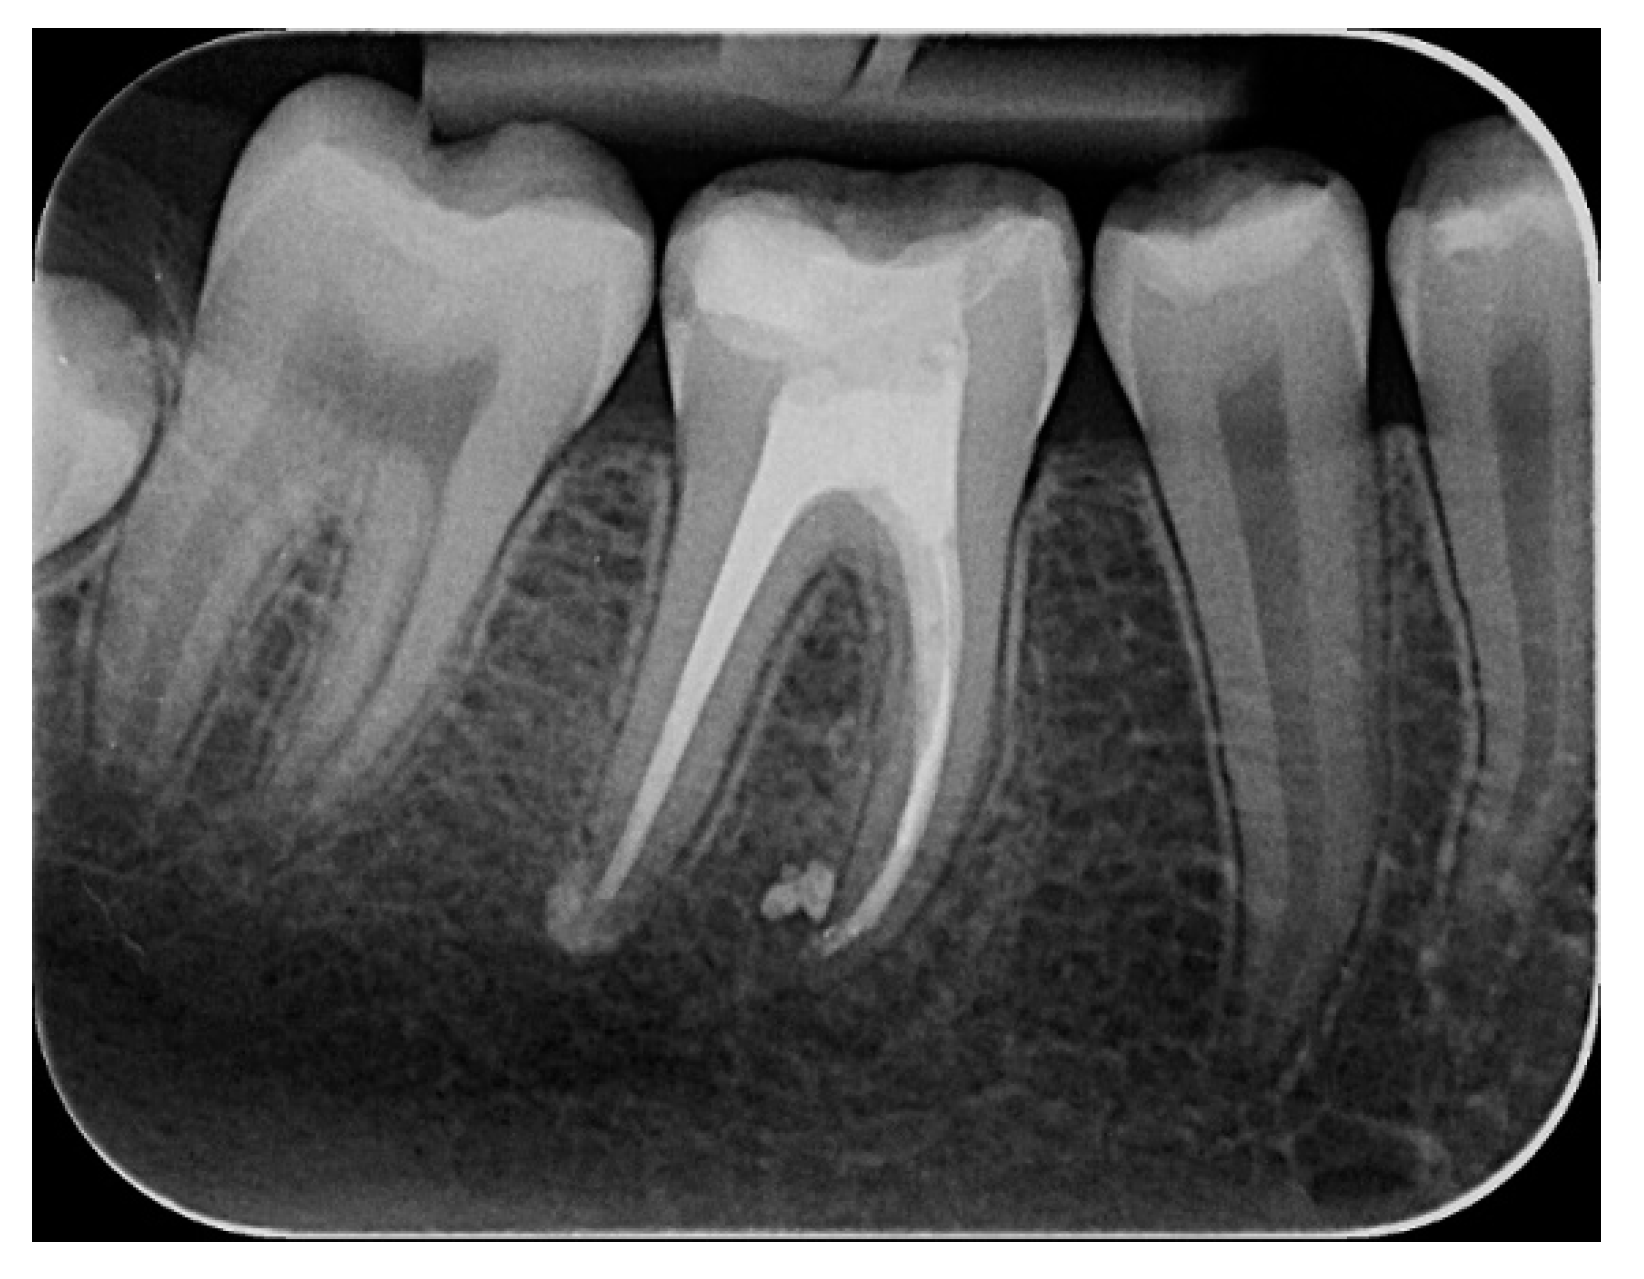

2.2.1. Chemomechanical Debridement of Endodontic Space and Root Canal Filling

2. Materials and Methods

2.1. Study Participant